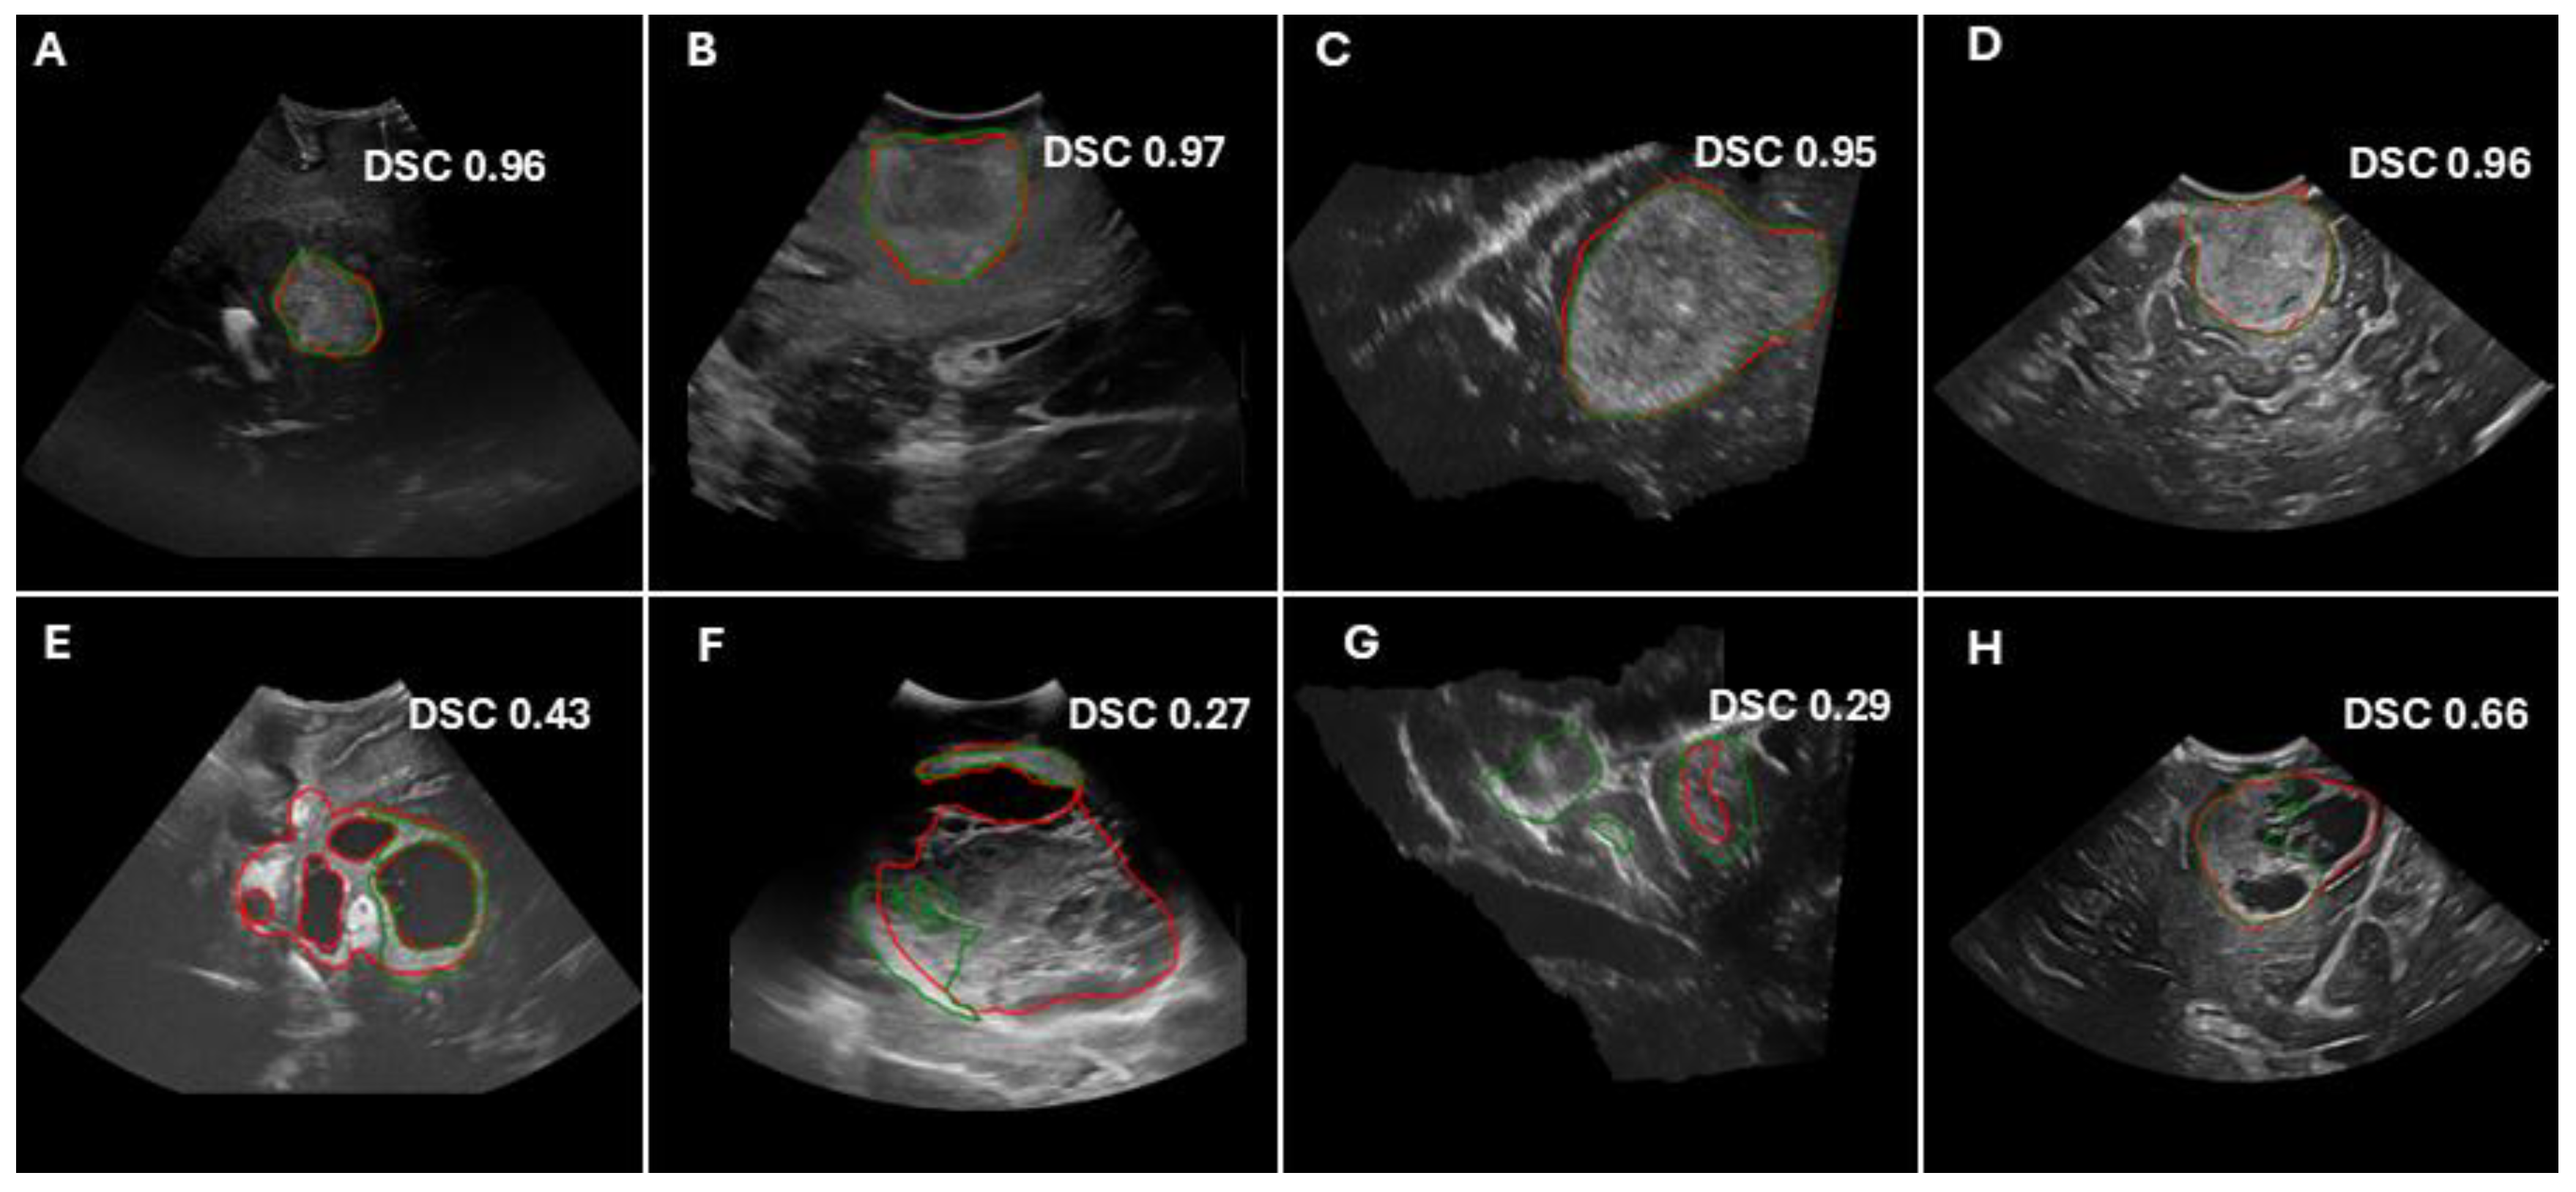

Figure 4.

Examples of model predictions and Dice similarity score (DSC) values for the hold-out test cohorts (A,B,E,F), as well as the external validation cohorts (C,G) (RESECT-SEG) and (D,H) (Imperial-NHS). The top panels show cases with good performance, whereas the bottom panels illustrate cases with poor performance. The ground truth tumor segmentations are delineated in red contours, whereas predicted segmentations are shown in green.